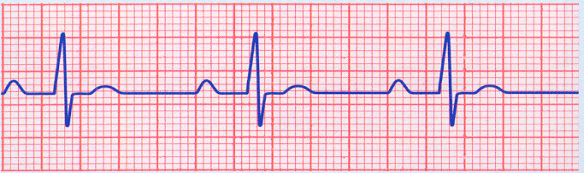

What’s the cause of this rhythm?

1st degree AV block